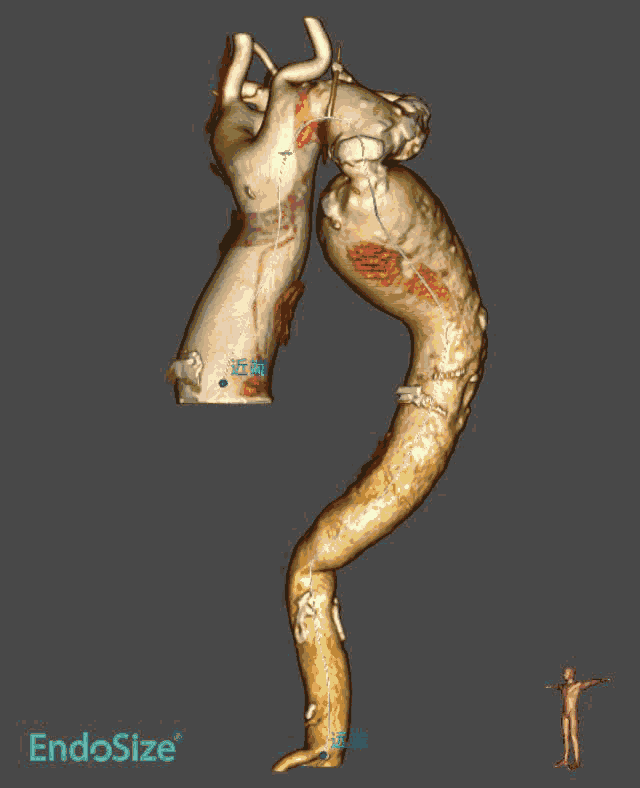

患者CT结果显示:主动脉瓣属于Type0型二叶瓣,重度狭窄并钙化,整个主动脉段非常扭曲,且在胸主动脉段有严重缩窄合并巨大主动脉瘤,双侧下肢动脉入路狭窄。同时,患者术前心脏超声提示心功能值(EF)仅17%,手术风险极高,国内外并无可供参考的手术方案和经验分享。

针对这位患者的特殊病情,在术前的多学科会诊中,我院结构性心脏病学组的钟炜教授首次提出“一站三式”的手术方案,即经颈动脉主动脉瓣置换术(TAVR)联合胸主动脉腔内修复术(TEVAR)联合经皮球囊主动脉缩窄血管成形术(PBACA)同步开展。